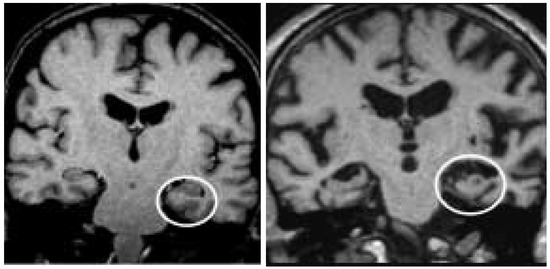

Magnetic resonance imaging in dementia

by Philip Scheltens

Swiss Arch. Neurol. Psychiatry Psychother. 2004, 155(7), 299-308; https://doi.org/10.4414/sanp.2004.01524 - 1 Jan 2004

Dementia is a clinical syndrome that has many causes. Structural neuroimaging is needed to refine differential diagnosis and identify comorbidity. Excluding structural lesions remains an important indication for either a CT or MR scan in an individual with cognitive decline, particularly if the [...] Read more.

Dementia is a clinical syndrome that has many causes. Structural neuroimaging is needed to refine differential diagnosis and identify comorbidity. Excluding structural lesions remains an important indication for either a CT or MR scan in an individual with cognitive decline, particularly if the presentation is in any way unusual. The ability of CT, if done appropriately with negative angulation and thin slices, and MRI to detect even subtle medial temporal lobe atrophy helps to diagnose Alzheimer’s disease and differentiate it from normal aging and non-dementia (i.e. depression) but does not rule out other dementias. Absence may indicate dementia with Lewy bodies if fitting with the clinical suspicion. The sensitivity of MRI to detect vascular pathology aids tremendously to the distinction between Alzheimer’s disease and vascular dementia, but has also learnt that overlap syndromes between the two conditions exist. Definite progress is being made in distinguishing normal aging from neurodegeneration using serial scans.The pattern of atrophy may indicate a focal dementia rather than Alzheimer’s disease. Clinically useful measures that distinguish the different neurodegenerative disorders from each other at an early stage are still awaited. MRI is increasingly being used to predict incipient dementia in subjects with mild cognitive impairment and as such the presence of medial temporal lobe atrophy has more predictive value for Alzheimer’s disease than any other measure. Imaging research is also likely to focus on measuring progression and detecting therapeutic effect. Hence, MRI is already being used in clinical trials in mild cognitive impairment, Alzheimer’s disease and vascular dementia. MRI is increasingly seen as an essential investigation in dementia. Unless and until novel biomarkers are found that can reliably detect and track the underlying pathological processes in the different dementias, MRI will continue to play an important role in the diagnosis of patients with dementia and in research into treatments. Full article